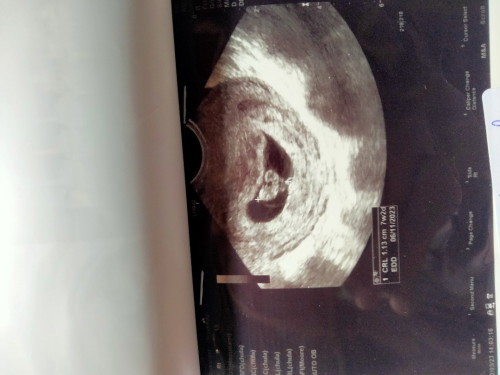

7สัปดาห์ค้ะ